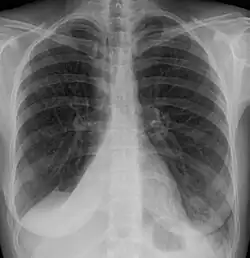

Atelectasis of a person's right lung

Atelectasis of the right lower lobe seen on chest X-ray.

Clinically significant atelectasis is generally visible on chest X-ray; findings can include lung opacification and/or loss of lung volume. Post-surgical atelectasis will be bibasal in pattern. Chest CT or bronchoscopy may be necessary if the cause of atelectasis is not clinically apparent. Direct signs of atelectasis include displacement of interlobar fissures and mobile structures within the thorax, overinflation of the unaffected ipsilateral lobe or contralateral lung, and opacification of the collapsed lobe. In addition to clinically significant findings on chest X-rays, patients may present with indirect signs and symptoms such as elevation of the diaphragm, shifting of the trachea, heart and mediastinum; displacement of the hilus and shifting granulomas.[13]